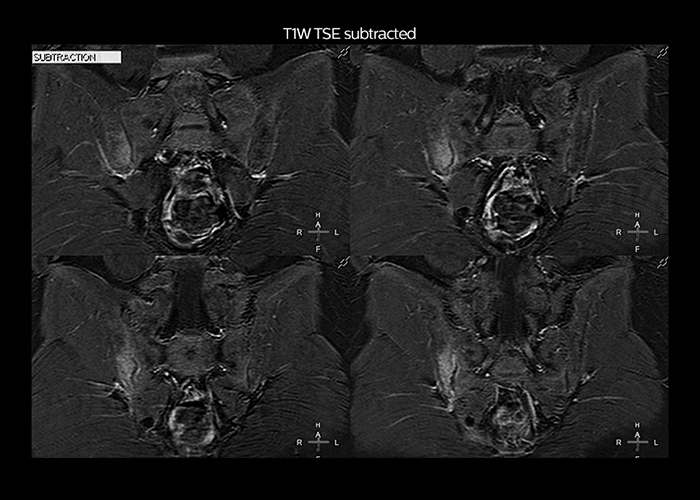

“To avoid coil changes we plan examinations of similar anatomies back to back, such as head and spine. Multiva helps us here a lot because coils don’t need to be changed frequently. Moreover, thanks to parallel imaging technology and 16-channel HeadSpineTorso and 8-channel MSK coils we are able to achieve excellent image quality. In this way Multiva helped us to increase both image quality and productivity.”

“Neurological cases, such as brain and spine imaging, represent the largest share in our MR scanning, followed by musculoskeletal cases. In general, we use simple and basic imaging protocols. But occasionally, we use advanced techniques for problematic cases if necessary.

“Most important, Multiva satisfies our clinical imaging needs very well,” says Mr. Tuna. “Many features of Multiva have become similar to the Ingenia system. Even in more complex imaging such as abdominal and cardiac, the image quality and performance of Multiva is better than we expected. General surgeons and physicians from our hospital’s internal medicine department prefer to refer to us because of this.”